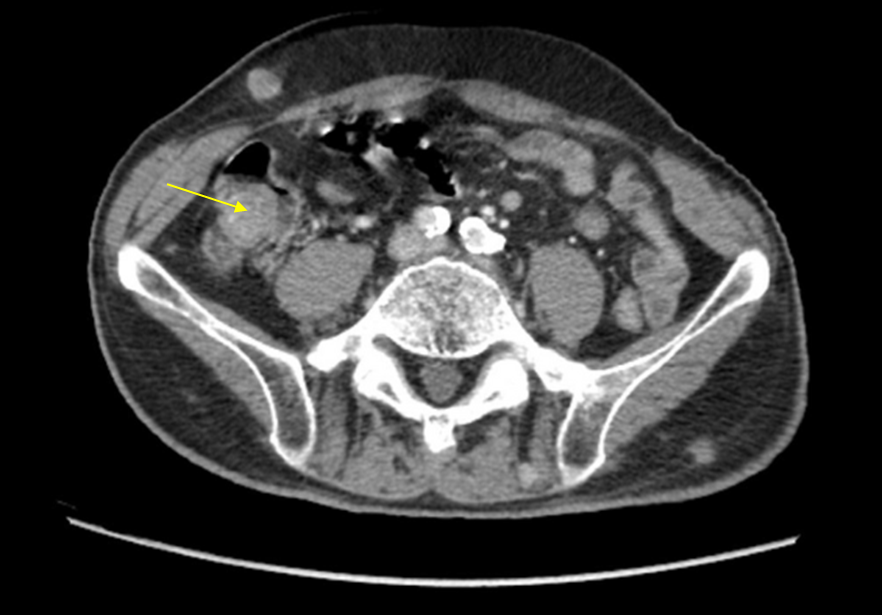

Img | CT1: Subcutaneous nodule CT2: Colon mass, extending to peritoneum |

종양표지자 상승, Sister Mary Joseph node로 추정되는 진찰소견, CT상 보이는 colon mass로 보아 대장암 의심 하, 진단 및 생검을 위해 대장내시경을 시행한다.

• 왼쪽 배꼽 주변에 2.5 cm 크기의 덩이가 있다. 단단하고 고정되어 있다는 점에서 악성 종양의 전이에 의한 덩이일 가능성을 고려해야 한다. 위와 같은 특징을 보이는 nodule을 Sister Mary Joseph nodule이라고 부르며, 소화기의 악성 종양의 전이를 시사한다.

• 복부덩이와는 별개로 RLQ 통증을 호소하는데, CT상 해당 부위에 colon mass가 확인되며, 이 mass의 끝부분이 peritoneum 쪽으로 퍼져 있는 양상이 보인다.

• 종양표지자인 CEA와 CA 19-9가 상승되어 있으므로 대장암의 가능성이 높다.

• 이를 육안적으로 확인하고 조직검사를 통해 확진 및 치료계획 수립을 위해 대장내시경을 시행해야 한다.